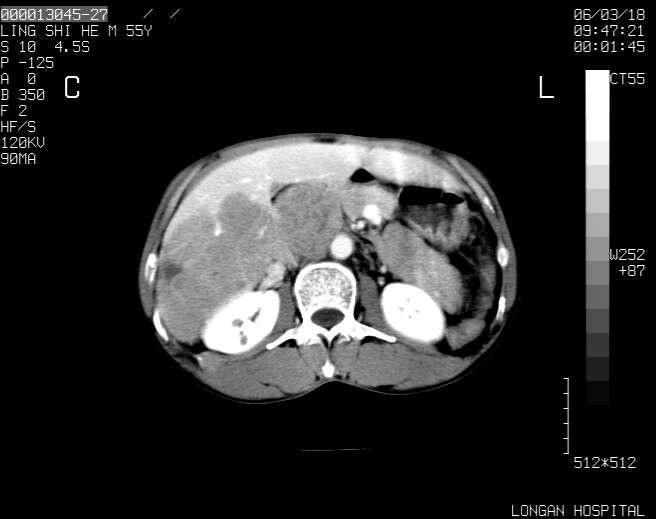

以下是引用guzhongliangddd在2006-3-21 22:13:00的发言:[br]病灶主要位于肝右叶的后份,内见异常血管,门脉主干及右支受侵{提示有癌栓形成},门腔间隙内见增大淋巴结。肝左叶内未见异常。

以下是引用zhuxinli在2006-3-22 1:23:00的发言:[br][br] 病灶主要位于肝右叶的后份,内见异常血管 .门脉右支截断,右叶前段早期强化(考虑动静脉漏),腹膜后肿大淋巴结,病灶逐渐强化,考虑为胆管细胞癌[br]